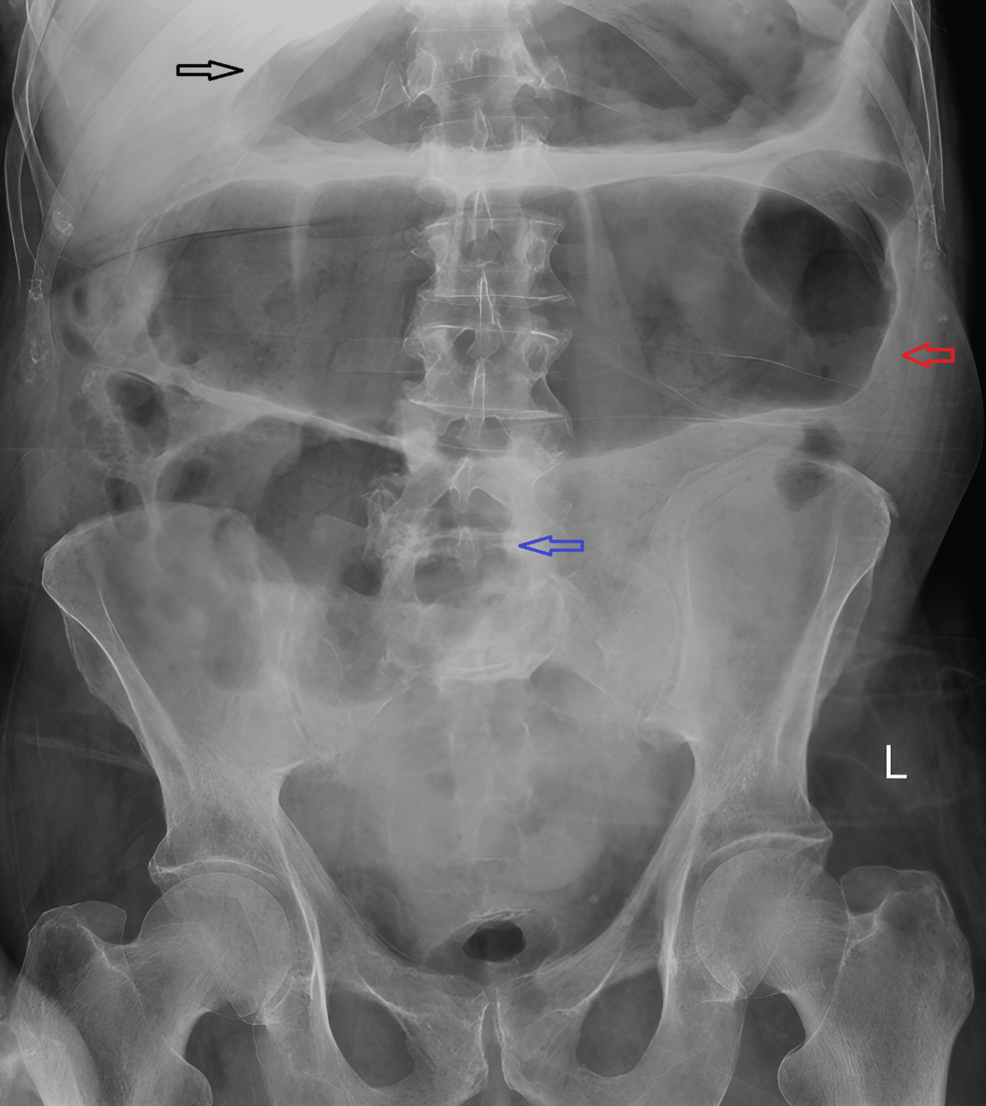

El megacolon tóxico es una complicación grave de la colitis, caracterizada por una dilatación masiva del colon. La infección por C. difficile es una causa común de colitis, pero la ausencia de toxinas detectables en este caso plantea interrogantes sobre los mecanismos subyacentes a la enfermedad en este paciente.